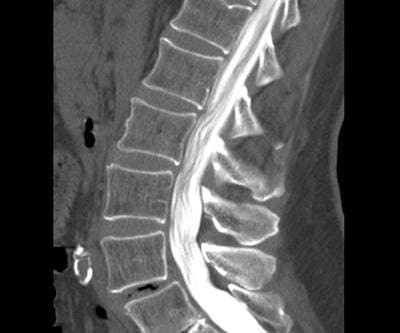

Кифопластика для восстановления позвоночника при компрессионных переломах

Компрессионный перелом позвонка вызывает сильную боль и ограничивает движения. Кифопластика — это малоинвазивный метод, который быстро снимает боль, восстанавливает высоту позвонка и возвращает к активной жизни.

Ламинэктомия: полное руководство по операции для освобождения спинного мозга

Вам назначили ламинэктомию или вы рассматриваете ее как вариант лечения? Эта статья подробно объясняет суть операции, показания, риски и все этапы восстановления, чтобы вы могли принять взвешенное решение о здоровье своего позвоночника.

МР-картина дистрофических изменений пояснично-крестцового...